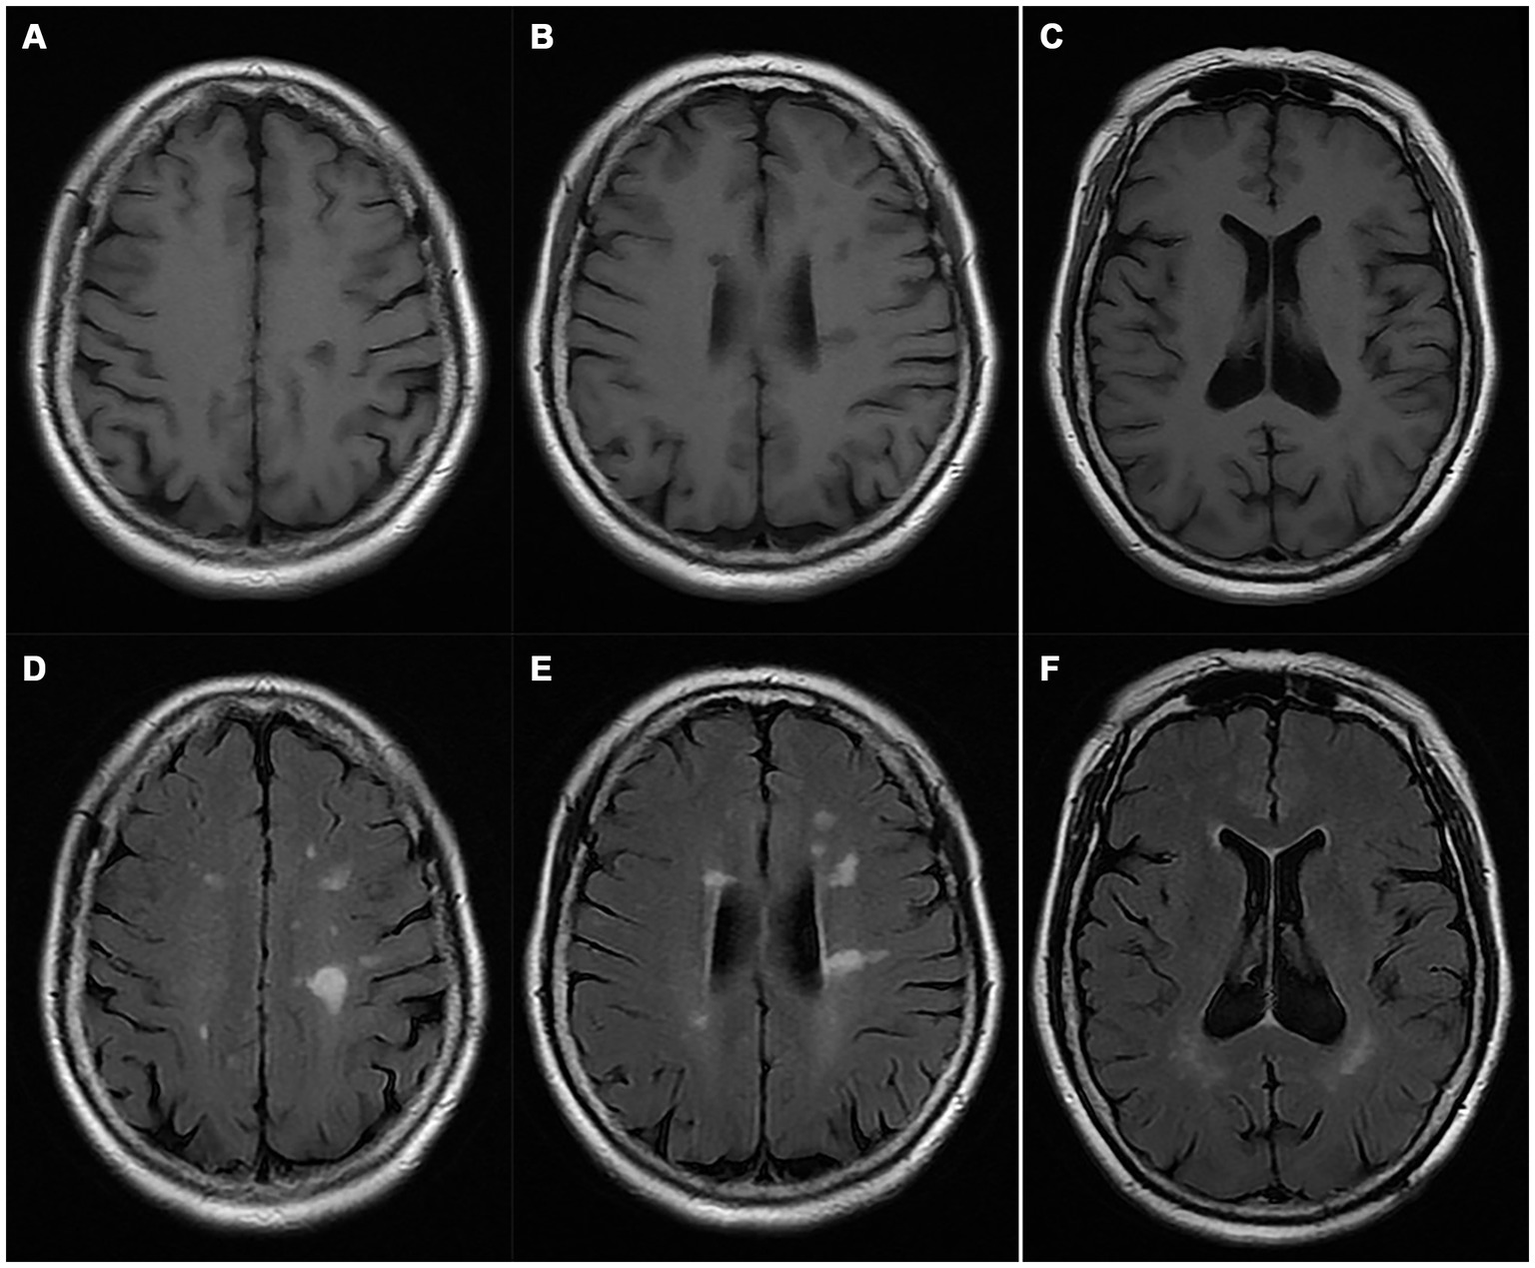

A pedigree chart for HSP in the family is shown in Figure 1. The clinical features of the affected individuals are summarized in Table 1, and the neuroimaging findings for the participants are shown in Figures 2A–F.

Figure 2

Magnetic resonance imaging of the proband (I-2). (A–C) T1WI; (D–F) T2 FLAIR images.

| MRI findings | See Figure 2 | Non significance | Not assessed |

Typical clinical manifestations of HSP include progressive spasms, lower limb weakness, bladder dysfunction, and a mild degree of physical dysfunction (10). The paradigmatic pathogenic involvement of HSP consists of the degeneration of CST axons and fasciculus gracilis fibers (37, 38). The pathogenic mechanisms associated with the clinical features and imaging abnormalities of HSPs vary substantially depending on the affected gene. ITPR1 gene mutations have long been recognized to cause non-progressive cerebellar ataxia and delayed motor development, known as SCAs (especially SCA 15 and 29) and GLSP. ITPR1-associated cerebellar dysfunction usually becomes apparent within the first year of life, and ITPR1-associated SCA pathogenic involvement generally causes the degeneration of CST axons (27, 39). Therefore, delayed motor development and the absence of pyramidal dysfunction are hallmarks of SCAs. Overall, approximately 75% of the individuals with SCA 29 exhibit learning difficulties (27). However, SCA15 typically does not present with an abnormal gait until adulthood, and the affected individuals remain ambulatory for several decades after diagnosis, which is, to some extent, a condition like that of the affected individuals in this family. The affected family members in this study were devoid of delayed motor development, pyramidal signs, and intelligence deficiency, nor did they present features such as nystagmus, ataxia, postural tremor, dysarthria, and hypotonia that are generally found in SCAs or GLSP. They did not present with aniridia, or severe pontine and cerebellar hypoplasia mimicking a diagnosis of PCH or PCH supporting GLSP neither, nor did they present typical MRI findings of PCH or SCAs. Instead, all three symptomatic individuals manifested typical spastic gait, hyperactive tendon reflexes, and pyramidal signs, and ach generation of this family included patients or carriers of the mutant variant, regardless of sex, suggesting that its inheritance pattern is consistent with autosomal dominant inheritance and that this was a pure ADHSP family.